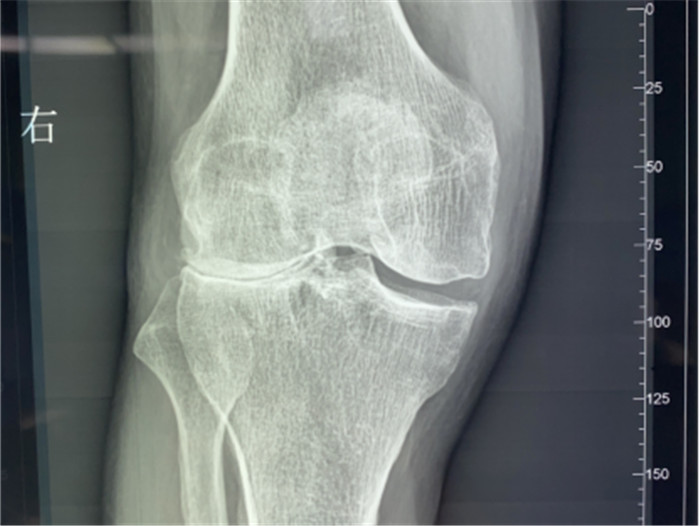

▲右膝關(guān)節(jié)外翻畸形

接診后羅軍主任詳細(xì)檢查病人,發(fā)現(xiàn)病人疼痛癥狀主要集中在膝關(guān)節(jié)外側(cè)間室,右下肢有明顯外翻畸形。這些癥狀都是單髁置換的適應(yīng)癥。雙下肢全長攝片和右膝內(nèi)翻、外翻位攝片顯示,膝關(guān)節(jié)外側(cè)間隙消失,膝外翻畸形,果不其然印證了上述臨床表現(xiàn)。收治入院后,羅主任團(tuán)隊決定為患者實施微創(chuàng)膝關(guān)節(jié)外側(cè)單髁置換術(shù),盡全力為張大爺解除病痛的折磨。